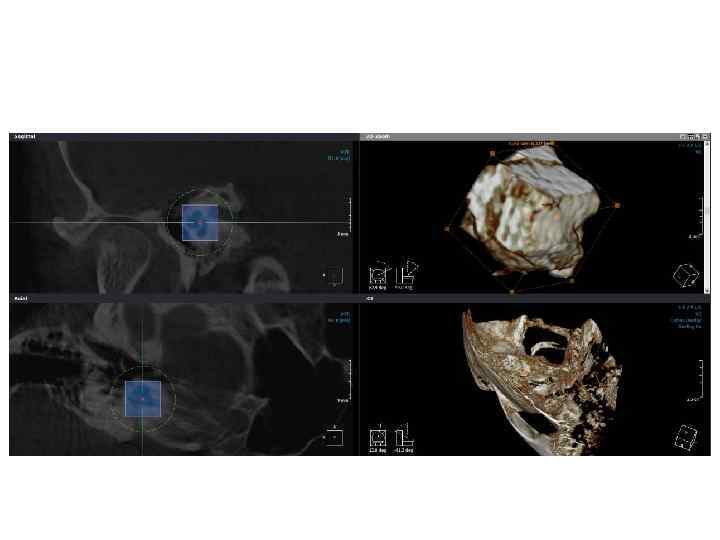

Метод объемной визуализации Inobitec Dicom Weaver (КЛКТ) Метод объемной визуализации Inobitec Dicom Weaver (КЛКТ)

Метод объемной визуализации Inobitec Dicom Weaver (МСКТ, 1 мм) Метод объемной визуализации Inobitec Dicom Weaver (МСКТ, 1 мм)

Метод объемной визуализации Point. Nix Real. Scan 2. 0 (КЛКТ) Метод объемной визуализации Point. Nix Real. Scan 2. 0 (КЛКТ)

Выводы • Методы МСКТ и КЛКТ обладают одинаковой информативностью в 2 D-визуализации анатомических структур Выводы • Методы МСКТ и КЛКТ обладают одинаковой информативностью в 2 D-визуализации анатомических структур пирамиды височной кости, несмотря на разную разрешающую способность. • Метод КЛКТ позволяет осуществлять 3 Dвизуализацию анатомических структур (слуховых косточек, улитки, каналов) пирамиды височной кости благодаря высокой разрешающей способности. • Метод КЛКТ оказывает в 5 -10 раз меньшую лучевую нагрузку на организм пациента по сравнению с МСКТ. • Для проведения полного исследования височных костей при КЛКТ необходимо 2 серии снимков, по одному на височную кость. Большинство аппаратов КЛКТ технически не приспособлены к проведению исследования височных костей.

Выводы • Inobitec DICOM Weaver обладает возможностью 3 D-визуализации пирамиды височной кости, однако его Выводы • Inobitec DICOM Weaver обладает возможностью 3 D-визуализации пирамиды височной кости, однако его функции ограничены отсутствием необходимых программных инструментов. • Возможности КЛКТ в сочетании с Point. Nix Real. Scan позволяют проводить визуализацию мелких структур пирамиды височной кости.